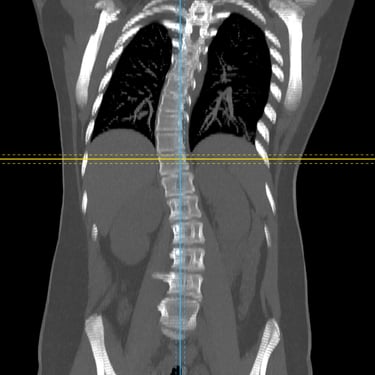

La escoliosis del adolescente idiopática del es una curvatura anormal de la columna vertebral que aparece durante el crecimiento, sin causa identificable. Su diagnóstico se realiza mediante evaluación clínica y estudios por imágenes, principalmente radiografías de columna completa, que permiten medir el ángulo de Cobb y determinar la magnitud de la desviación. En casos complejos o con sospecha de compromiso neurológico, se utiliza resonancia magnética para descartar anomalías medulares. La detección temprana es clave para definir el tratamiento adecuado —observación, uso de corsé o cirugía— y prevenir la progresión de la deformidad.